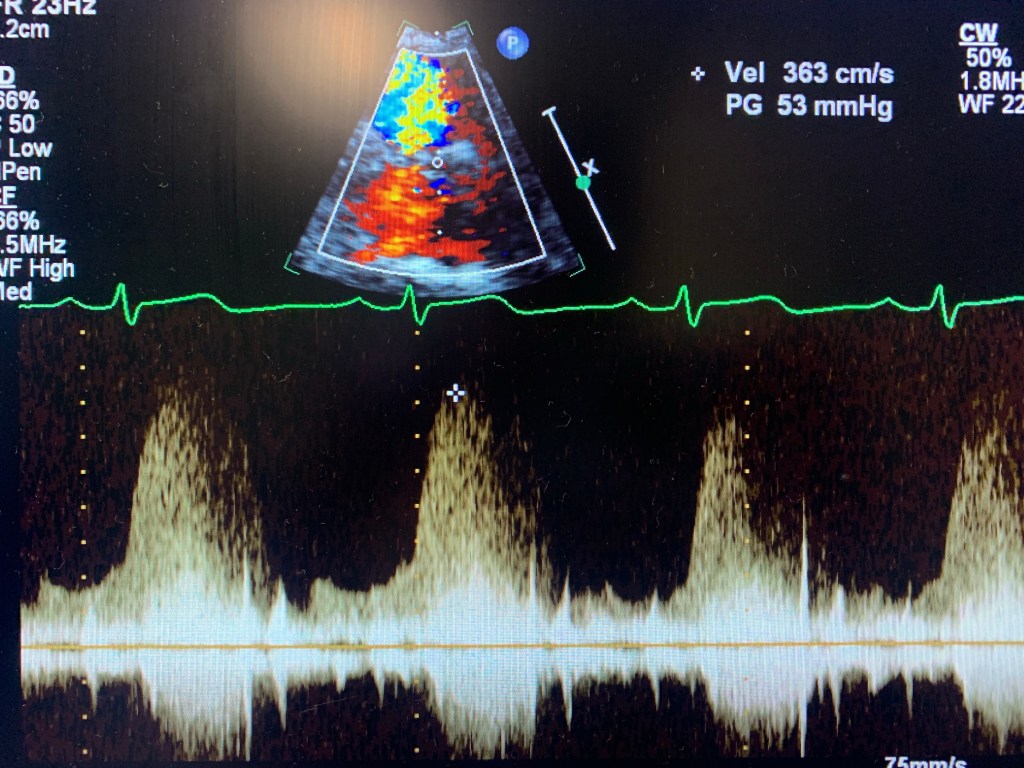

Echocardiogram of a VSD

Case study: a 32 y/o female, w/ shortness of breath, known VSD.

I knew about the problem since the patient told me about it and it was mentioned in the chart. I started with Parasternal Long axis and looked for a flow by using Doppler. Once I found it, I used PW and CW to get the velocity. Then moved to Parasternal Short. Since the VSD was at 11 o’clock, it was an indication that it was a perimembranous VSD. Use color Doppler, lower the scale, take pictures and PW and CW too. Same in Apical 4, 5 and 3. Later I went to ask the MD if they needed contrast. Which I used later. Don’t have pictures here because the color Flow didn’t look good. But I had similar velocity. And always try a higher window at the parasternal. Instead of PEN, use GEN. The color Doppler will look better.